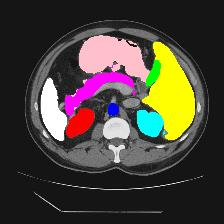

Medical image segmentation is one of the most fundamental tasks concerning medical information analysis. Various solutions have been proposed so far, including many deep learning-based techniques, such as U-Net, FC-DenseNet, etc. However, high-precision medical image segmentation remains a highly challenging task due to the existence of inherent magnification and distortion in medical images as well as the presence of lesions with similar density to normal tissues. In this paper, we propose TFCNs (Transformers for Fully Convolutional denseNets) to tackle the problem by introducing ResLinear-Transformer (RL-Transformer) and Convolutional Linear Attention Block (CLAB) to FC-DenseNet. TFCNs is not only able to utilize more latent information from the CT images for feature extraction, but also can capture and disseminate semantic features and filter non-semantic features more effectively through the CLAB module. Our experimental results show that TFCNs can achieve state-of-the-art performance with dice scores of 83.72\% on the Synapse dataset. In addition, we evaluate the robustness of TFCNs for lesion area effects on the COVID-19 public datasets. The Python code will be made publicly available on https://github.com/HUANGLIZI/TFCNs.

翻译:医学图像分解是医学信息分析的最根本任务之一,到目前为止已经提出了各种解决办法,包括许多深层次的学习技术,如U-Net、FC-DenseNet等。 然而,高精度医学图像分解由于医疗图像中存在固有的放大和扭曲,以及存在与正常组织密度相似的损伤,因此仍是一项极具挑战性的任务。在本文件中,我们建议TFCN(全面革命稠密网络的传输者)通过向FC-DenseNet引进ResLear-Transerferent(R-Transerfor)和Culvacial线性关注区(CLAB)来解决这一问题。TFCN不仅能够利用CT图像中更多的潜在信息来提取特征,而且还能够通过CLAB模块更有效地捕捉和传播语性特征和过滤非神经性特征。我们的实验结果表明,TFCN可以在Syapseion/SymblyDDS上以83CN-72 ⁇ 的分数实现状态。此外,我们在Synapse-DRIS数据设置上,我们还将评估CUTFTFI/LIS的可靠度。